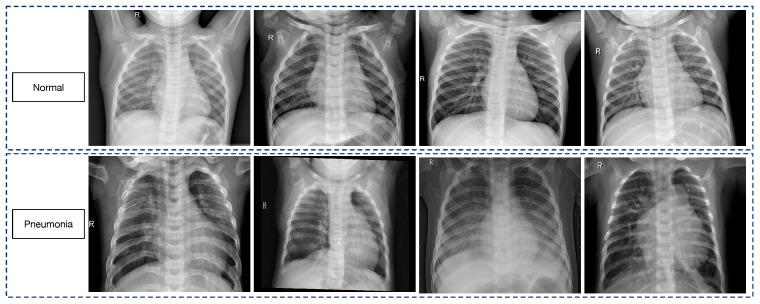

In the domain of AI-driven healthcare, deep learning models have markedly advanced pneumonia diagnosis through X-ray image analysis, thus indicating a significant stride in the efficacy of medical decision systems. This paper presents a novel approach utilizing a deep convolutional neural network that effectively amalgamates the strengths of EfficientNetB0 and DenseNet121, and it is enhanced by a suite of attention mechanisms for refined pneumonia image classification. Leveraging pre-trained models, our network employs multi-head, self-attention modules for meticulous feature extraction from X-ray images. The model's integration and processing efficiency are further augmented by a channel-attention-based feature fusion strategy, one that is complemented by a residual block and an attention-augmented feature enhancement and dynamic pooling strategy. Our used dataset, which comprises a comprehensive collection of chest X-ray images, represents both healthy individuals and those affected by pneumonia, and it serves as the foundation for this research. This study delves deep into the algorithms, architectural details, and operational intricacies of the proposed model. The empirical outcomes of our model are noteworthy, with an exceptional performance marked by an accuracy of 95.19%, a precision of 98.38%, a recall of 93.84%, an F1 score of 96.06%, a specificity of 97.43%, and an AUC of 0.9564 on the test dataset. These results not only affirm the model's high diagnostic accuracy, but also highlight its promising potential for real-world clinical deployment.

在人工智能驱动的医疗保健领域,深度学习模型通过X射线图像分析显著推进了肺炎诊断,从而表明医疗决策系统的效能有了重大进展。本文提出了一种新颖的方法,利用深度卷积神经网络有效地融合了EfficientNetB0和DenseNet121的优势,并通过一套注意力机制进行增强,以实现精确的肺炎图像分类。借助预训练模型,我们的网络采用多头自注意力模块从X射线图像中进行细致的特征提取。基于通道注意力的特征融合策略进一步提高了模型的集成和处理效率,该策略辅以残差块以及注意力增强的特征增强和动态池化策略。我们使用的数据集包含胸部X射线图像的全面集合,涵盖健康个体和肺炎患者,为这项研究奠定了基础。本研究深入探讨了所提出模型的算法、架构细节和操作复杂性。我们模型的实证结果值得关注,在测试数据集上表现出色,准确率为95.19%,精确率为98.38%,召回率为93.84%,F1分数为96.06%,特异性为97.43%,AUC为0.9564。这些结果不仅证实了模型的高诊断准确性,还突出了其在实际临床应用中的广阔前景。